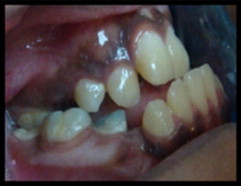

He encontrado un artículo de estudio de caso bastante interesante de A. Al-Jobair del Departamento de Odontología Pediátrica y Ortodoncia de la Facultad de Odontología de la Universidad Rey Saud, publicado en 2010. De este artículo destacaré sus partes más importantes. Este es un estudio de caso de una niña de 11 años de edad.

"La paciente parecía ser bien integrada, se la veía sana e inteligente, pero tenía dificultad para hablar. En su visita inicial tenía un tamaño de 100 cm de estatura. El examen extraoral reveló manifestaciones clásicas asociadas con la acondroplasia como ser: baja estatura, manos cortas y en tridente, prominencia frontal, puente nasal hundido, hipoplasia severa de la cara media y labios incompetentes. Se observó respiración bucal, brecha interlabial de aproximadamente 12 mm en reposo y una mente hiperactiva. El cierre de los labios no fue posible sin tensión muscular. También fue observado un perfil facial cóncavo, sin embargo, la mandíbula parecía normal y la barbilla no era prominente."

Intraoralmente, se observó macroglosia  un patrón de deglución con empuje de la lengua, gingivitis generalizada, mordida cruzada posterior, mordida abierta anterior (igual que la maloclusión) y una reacción invertida anterior. Había una relación molar dental clase III con apiñamiento (una de las complicaciones dentales más comunes en pacientes acondroplásicos) en la región maxilar anterior. La paciente tenía dentición mixta: tamaño, número y forma de los dientes era normal con múltiples lesiones y restauraciones de caries. La erupción de los dientes era compatible con la edad cronológica. La radiografía panorámica mostró un número completo de dientes permanentes, incluyendo terceros molares con desarrollo normal, apiñamiento en las regiones caninas y en los molares superiores. El análisis cefalométrico de la radiografía lateral del cráneo reveló que el maxilar era severamente retrognático (posición anormal del maxilar, cuando empuja hacia atrás, con relación al esqueleto facial y a los tejidos blandos), con la posición normal de la mandíbula, con la altura facial superior disminuida, con la altura facial inferior aumentada y con una relación esquelética de mandíbula de clase III. Dentalmente, los incisivos maxilares estaban reclinados y los incisivos mandibulares estaban normalmente inclinados. Se evaluó el riesgo de caries. El plan de tratamiento fue formulado tanto para extraer todos los dientes primarios cariados como para restaurar todos los dientes permanentes cariados. Se realizó el tratamiento dental según lo planificado, con anestesia local y la colaboración de la paciente. Esta fue colocada en un programa de visita al odontólogo a cada tres meses.

gr4 gr6 gr7